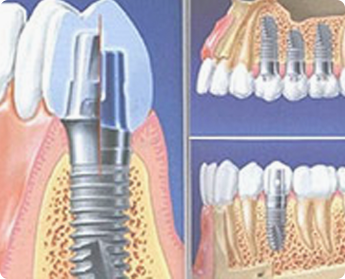

牙齿种植(Dental implant)指的是一种以植入骨组织内的下部结构为基础来支持、固位上部牙修复体的缺牙修复方式。包括下部的支持种植体和上部的牙修复体两部分,种植牙是近年来迅速发展起来的一种新型义齿修复方法,许多传统义齿难以解决的疑难案例通过种植义齿能得到较为理想的疗效,因此倍受客人的喜爱,逐渐成为牙缺失的优先修复方法。

通过计算机断层CT口腔体检,获取口腔的三维数据,3D精准化定位详细测量牙床的骨质密度、牙槽骨本身的高度、宽度等条件;模拟显示种植体在牙槽骨的位置,生成可视化的数据模板。根据数据模板由计算机辅助设计的种植手术导板,从而大大的监控种植牙手术的安全性和准确性。